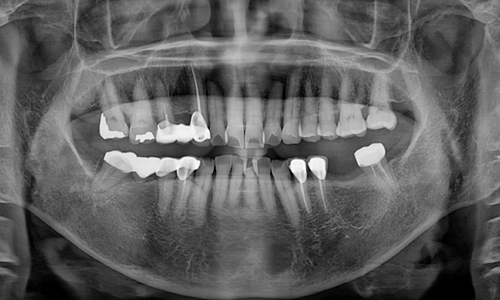

육안으로 볼 수 없는 치아 뿌리의 염증 확인

엑스레이는 육안만으로 확인 하기 어려운 치아의 손상도 또는 치아 뿌리 쪽의 염증 등을 확인할 수 있습니다.

전반적인 치조골 높이는 물론 눈에 띄지 않는 치주질환의 진단에 꼭 필요한 과정입니다.